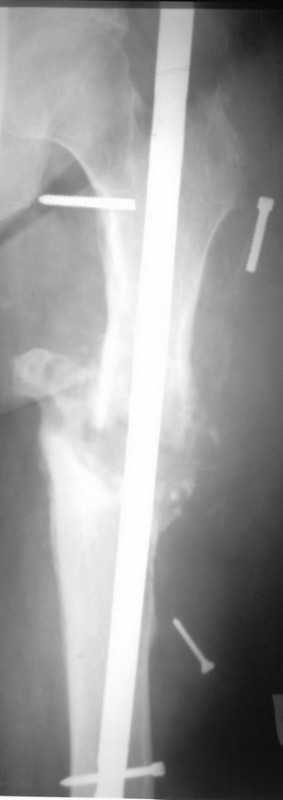

Здравствуйте уважаемые коллеги, прошу Вашего мнения относительно тактики лечения пациента М. 37 лет, рост 170 см. вес 140 кг. Анамнез: пострадал в рез. ДТП в 2004 году, лечился в одной из районных больниц гдебыл прооперирован DCP. в 2006 году перелом м/фиксатора с последующим реостеосинтезом стержнем Кюнчера без блокирования. в 2007 году перелом фиксатора после чего обратился в нашу клинику, где было произведено удаление гвоздя, БИОС L-360 mm D-12 mm с кортико-спонгиозной пластикой, в теч. 6-и мес. больной был под наблюдением динамизация ч-з 2 мес. после чего пациент исчез с поля зрения. Появился с жалобами на болезненность в месте перелома, укорочение ноги, в течении года поочередно в ягодичной области и н/3 бедра функционирующие свищи. На данный момент имеем свищ в н\3 бедра, укорочение ноги на 3 см, внешняя ротация.Произведена фистулография, взят посев из свищевого хода. Планируется: - Удаление м\фиксатора и всех винтов(за исключением проксимального) - I&D с рассверливанием до 16 мм. - кортикотомия, открытое устранение деформаций - БИОС стержнем L-360 mm D-12 mm с а.б. покрытием - бусы с ванкомицином в области свищей

Уважаемый Илья! Если я правильно понял, фистулография у Вас - вторая картинка, а ранки на первой фотографии в области нижних блокирующих винтов и приблизительно на уровне псевдоартроза. Хотелось бы уточнить, есть ли клинические проявления свища на уровне псевдоартроза, отделяемое и т. д. Это существенно влияет на план операции - если перелом неинфицирован,а инфекция только на уровне нижних блокирующих винтов, достаточно удалить конструкции, те, что доступны, не стоит гоняться за кончиками винтов, произвести остеосинтез по Илизарову (на уровне малого вертела стержни, конечно)с п о с т е п е нн о й коррекцией угловой и ротационной деформаций. Параллельно ревизовать место расположения нижнего блокирующего винта, рассверлить, почистить, дренировать.

Если же инфекция и внизу, и на уровне перелома, без тщательной ревизии его не обойтись, не исключено, что потребуется резекция большей или меньшей части диафиза, в последующем или сразу билокальный остеосинтез, что у больного с такими формами далеко не подарок. Или уж идти на укорочение, если резекция будет не очень большой, а после сращения и купирования остеомиелита удлинять, если он еще сам захочет. Успехов. Можете написать на mail, если хотите, вот адрес lobanov.in@gmail.com